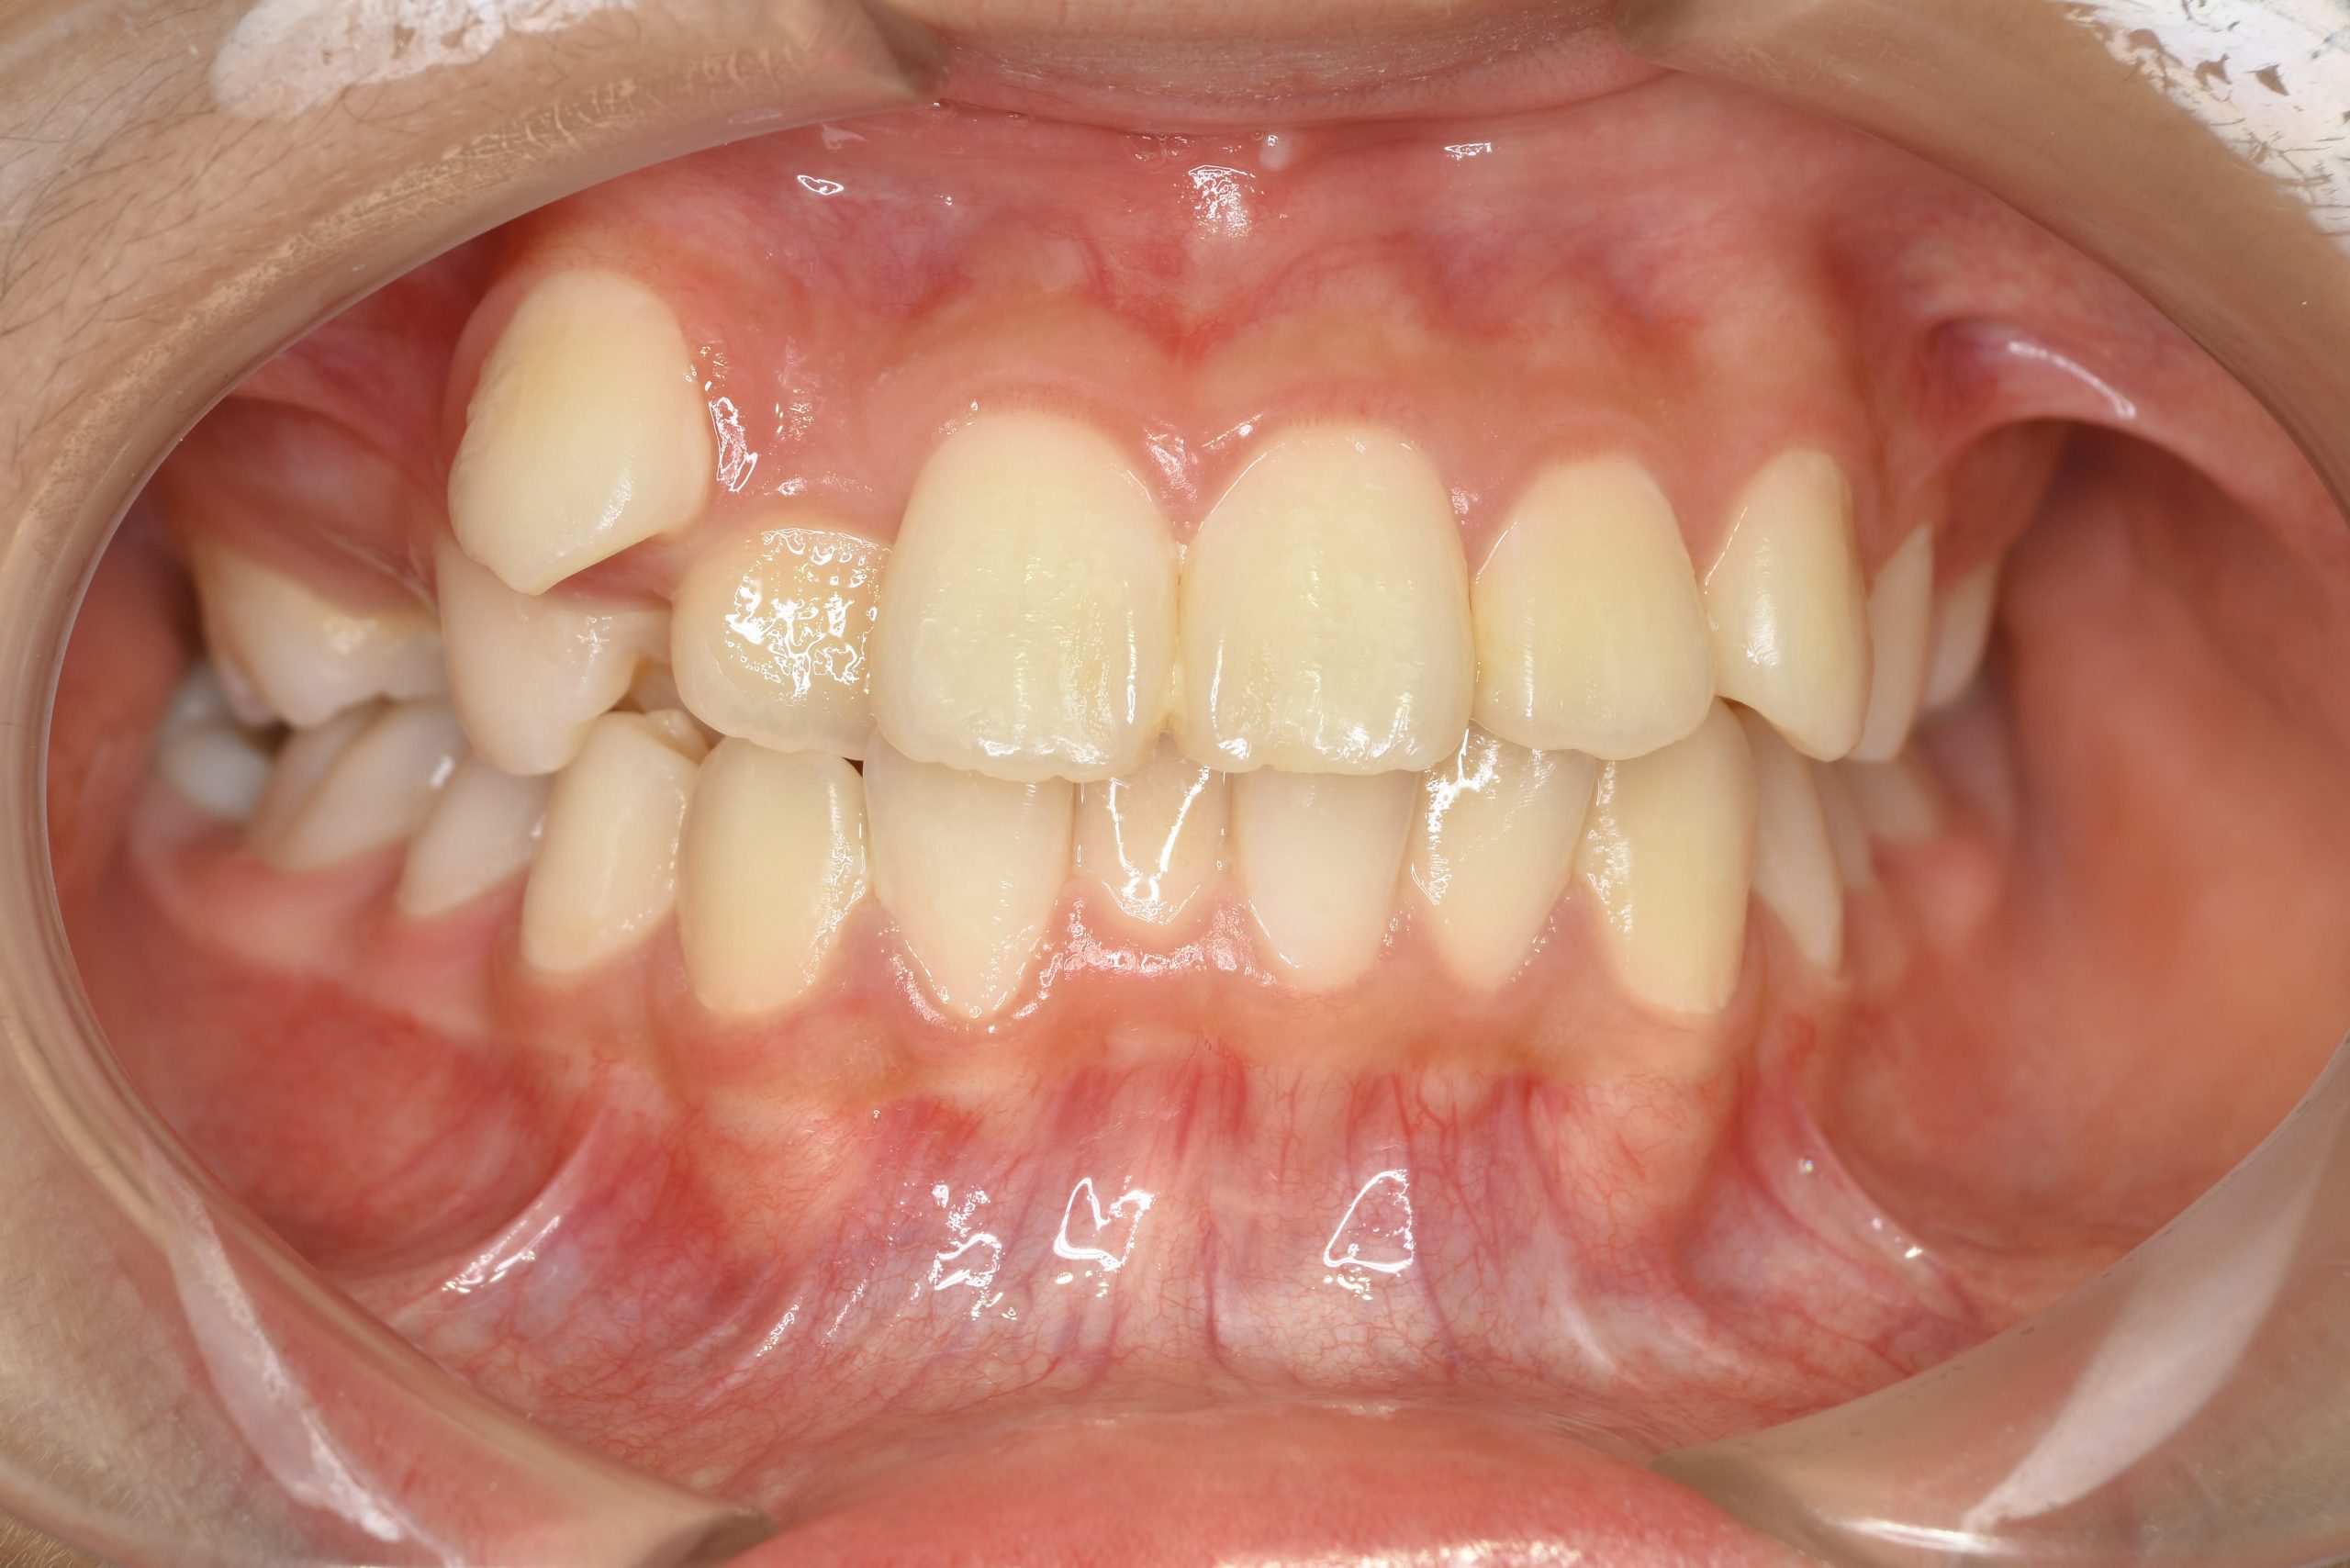

アフター

ワイヤー矯正治療|症例_1324

主訴 下顎が出ている

施術内容 MSEと下顎リンガルアーチを用いて上下顎骨を拡大した。

その後マルチブラケット装置を用いて非抜歯で歯牙を配列し、良好な咬合を獲得した。

治癒期間 1年5か月間